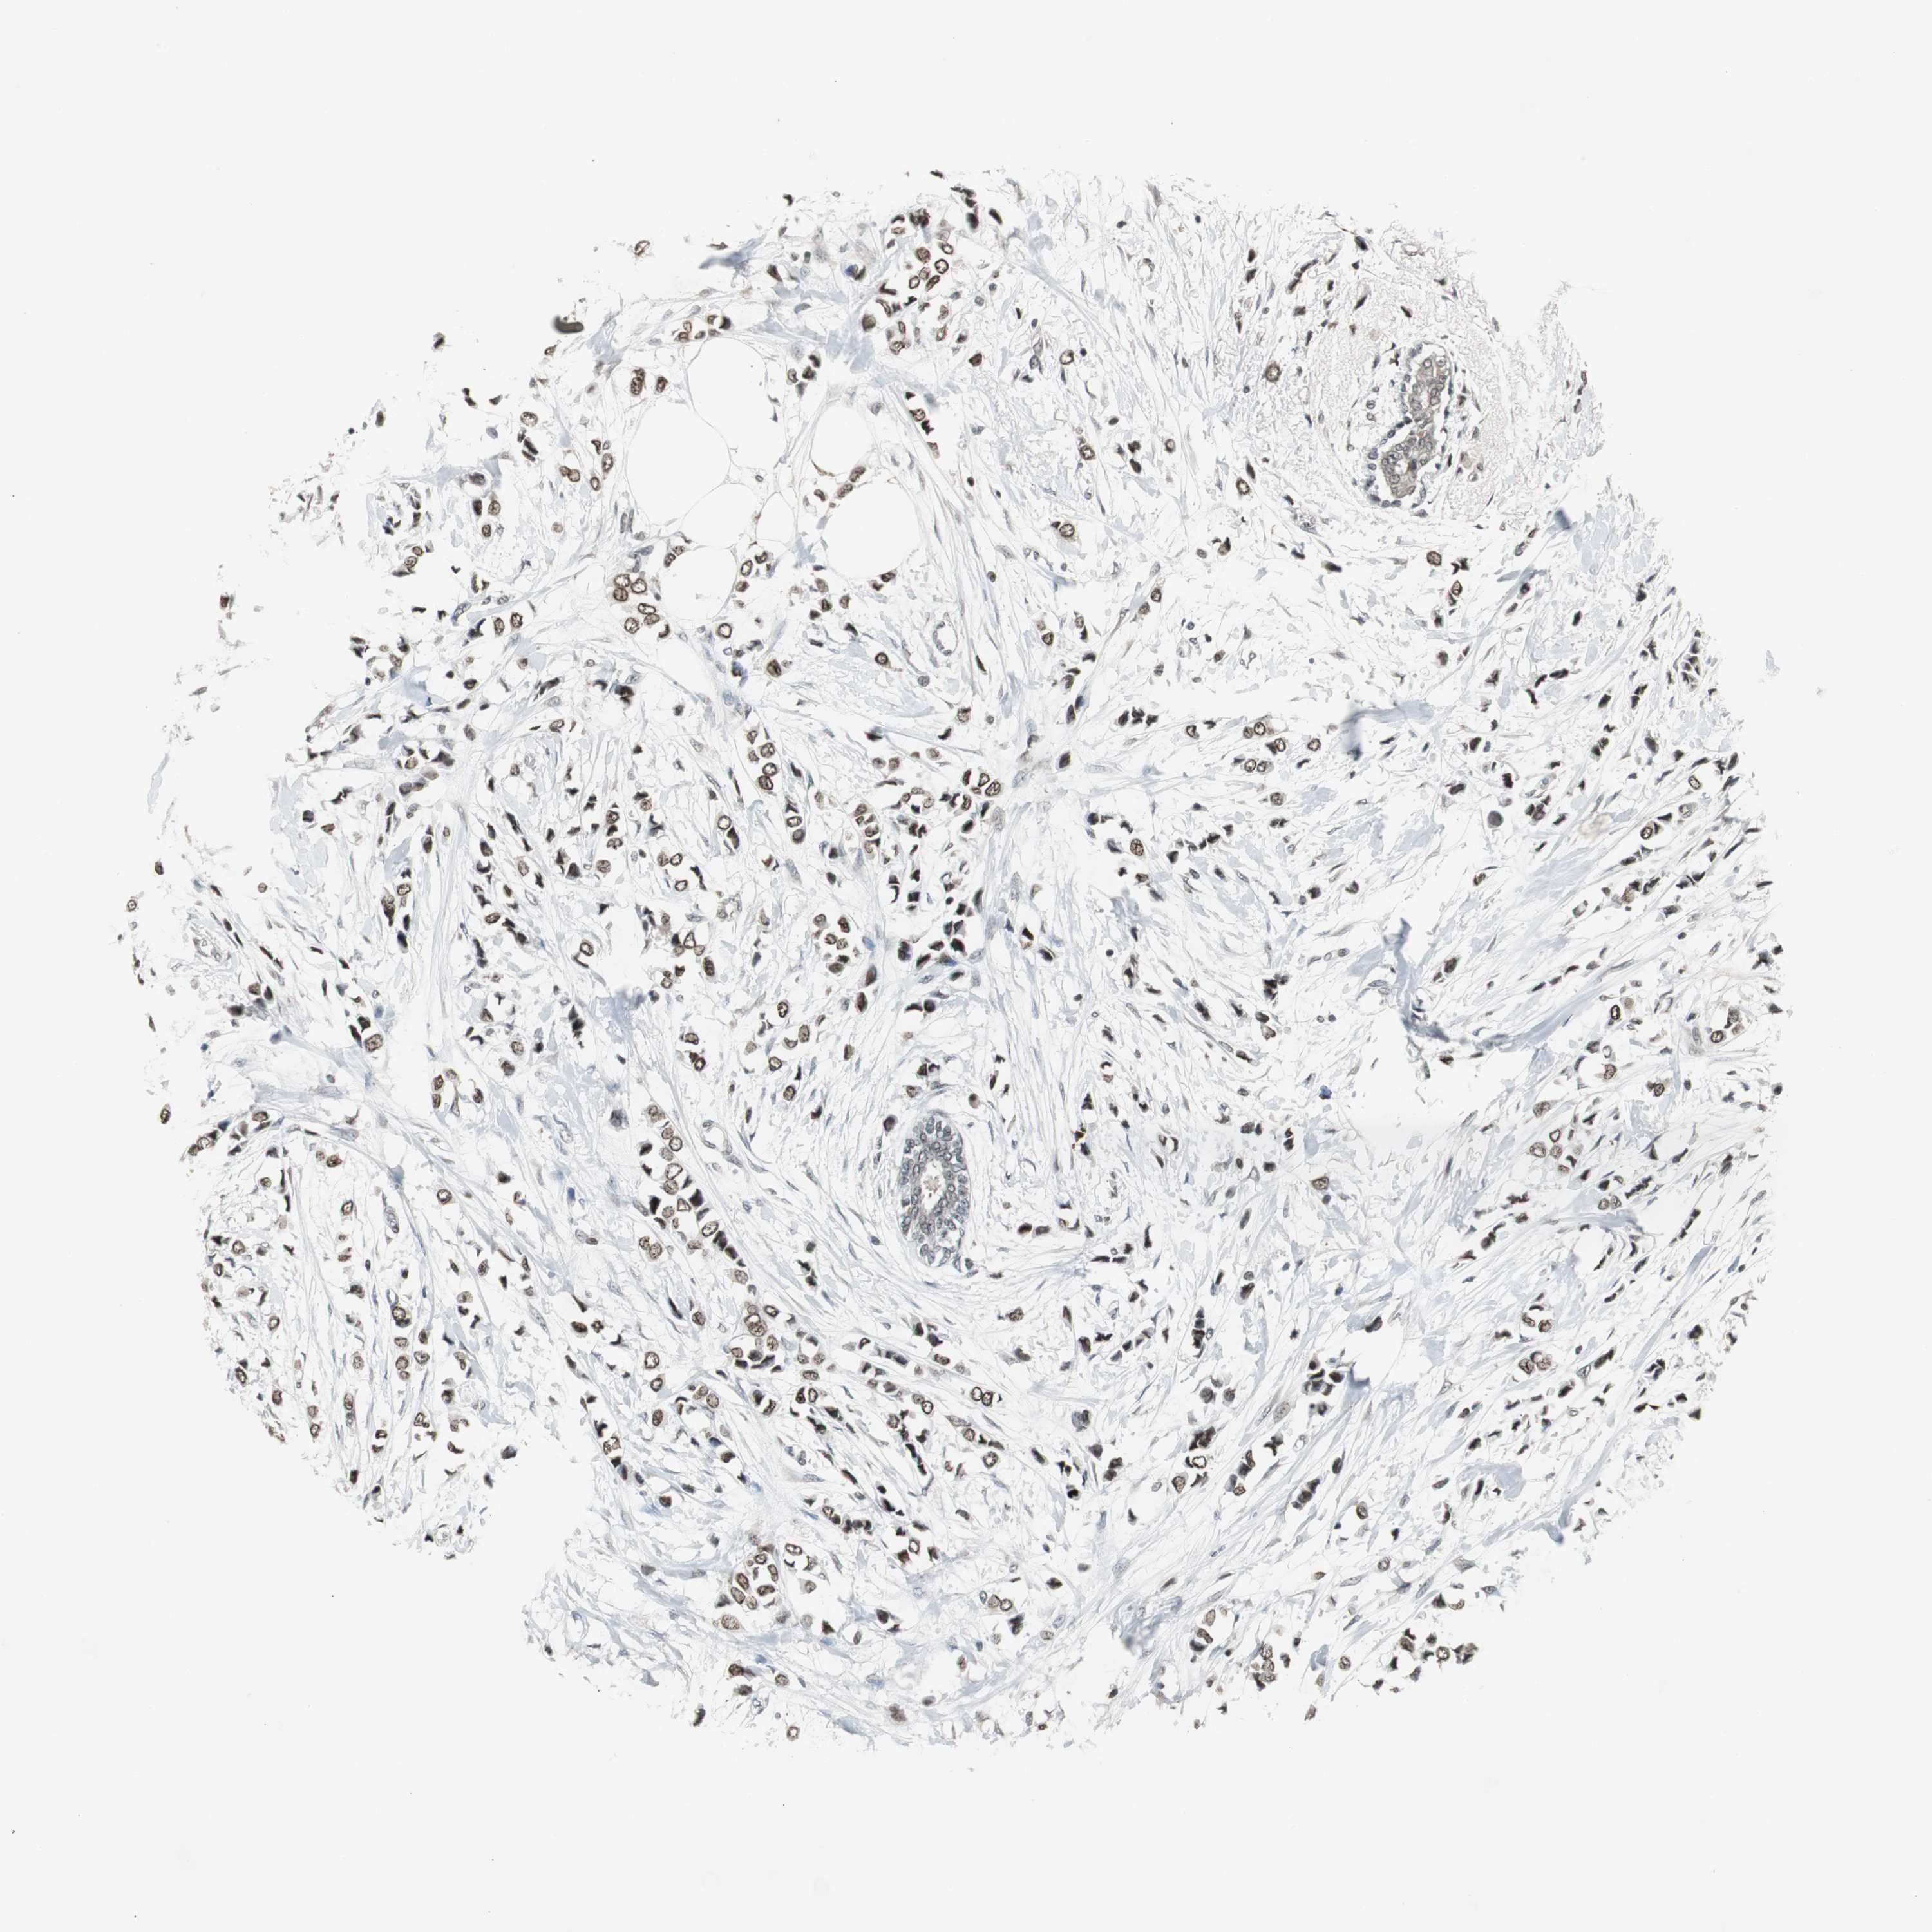

CANCER BREAST CANCER Show tissue menu

BRCA TCGA BRCA VALIDATION PROTEIN EXPRESSION